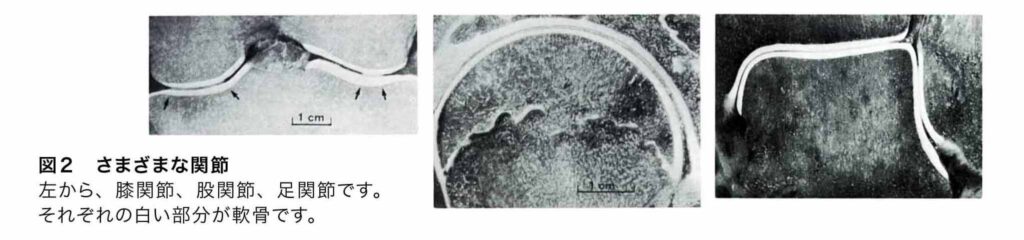

関節とは、骨と骨のつなぎ目の動く場所ですが、組織として、関節であるためには、骨端部の表面には、軟骨組織があり、同時に、関節包が存在することが、関節であることの必須の条件です。関節包のない骨のつなぎ目は、関節ではありません。

関節の構造を説明すると、関節は関節包に包まれています。その関節包の内側には、滑膜という膜が、関節の内腔に張りめぐらされています。滑膜では、関節液をつくっています。関節包に分布する血管やリンパ管から関節液の成分を濾過して、さらにムチン様成分(ヒアルロン酸)を分泌することによって、関節液がつくられています。

関節液は、滑膜から、関節内部に排出および、吸収されています。これにより、関節内は、常に新しい、関節液によって満たされています。関節内の軟骨細胞(図の赤い部分)は、関節液からの栄養と酸素を供給されることにより生きています。さらに関節が動く時には、関節軟骨表面が互いに密着し、こすれています。